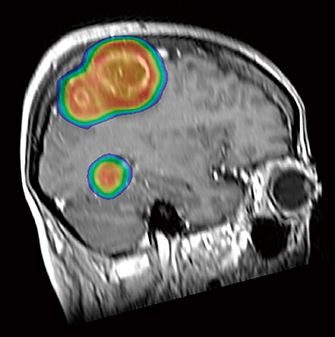

2.少数個の脳転移

複数の脳転移巣に1つ1つ定位放射線治療を行うと,病巣の個数が増えるにつれ治療時間が長くなるが,TrueBeam導入後は強度変調放射線治療(IMRT)で複数の脳転移巣を一括して短時間で治療できるようになり,さらに近接する脳転移巣があっても過線量の心配がなくなった(図3)。

図3 多発性脳転移に対する定位的IMRT

4個の脳転移巣(そのうち2個は隣接)を含む1つのplanning target volume(PTV)を設定し,4個の脳転移巣を3分で治療し得た。